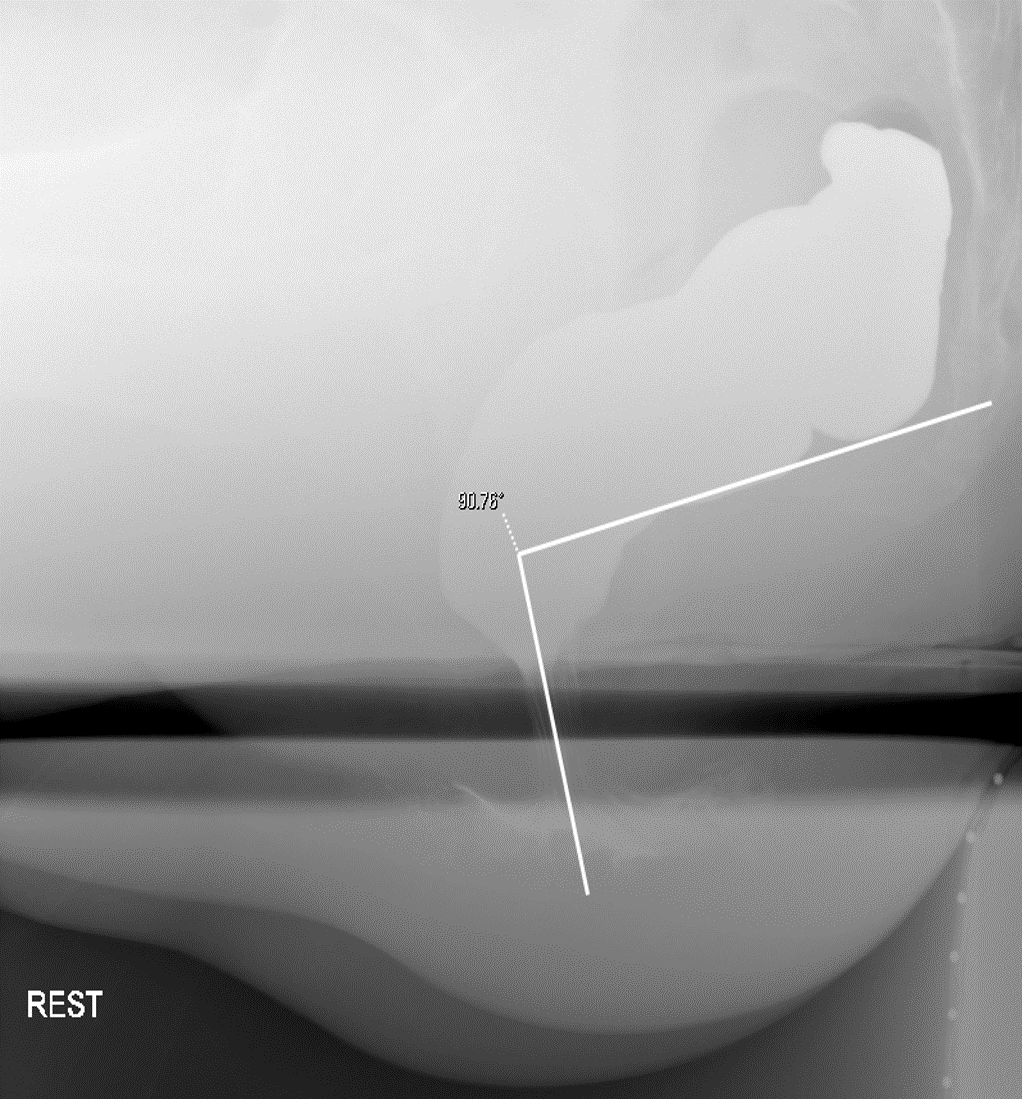

- Anorectal Angle (ARA)

- The ARA is the angle between a line drawn parallel to the posterior all of the rectal ampulla just above the impression of the puborectalis sling and a line drawn in the axis of the anal canal

(key image 7).

- Measure the ARA during rest, "squeeze," and defecation.

- Rest

(key image 8)